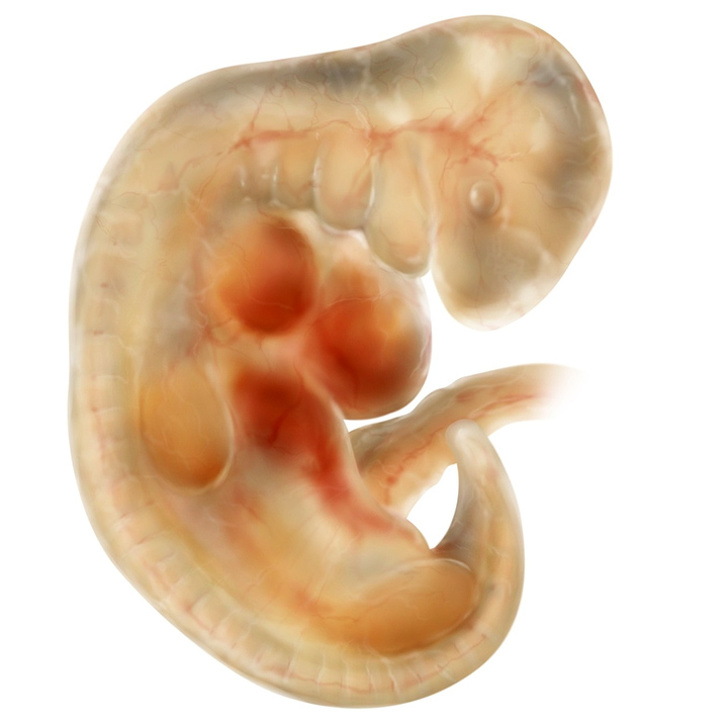

Ембріон на 4-му тижні вагітності.

Приблизно на 20-й день вагітності відбувається дуже важлива подія: з'являється нервова трубка, яка потім перетвориться у спинний і головний мозок дитини. Вже на 21-й день у нього починає битися серце і формуватися всі важливі органи, наприклад нирки і печінку. Очі поки не зайняли звичного положення — бульбашки, з яких вони потім оформляться, знаходяться з боків голови. До кінця 1-го місяця в ембріона з'являється кровоносна система, а хребет і м'язи починають свій розвиток.